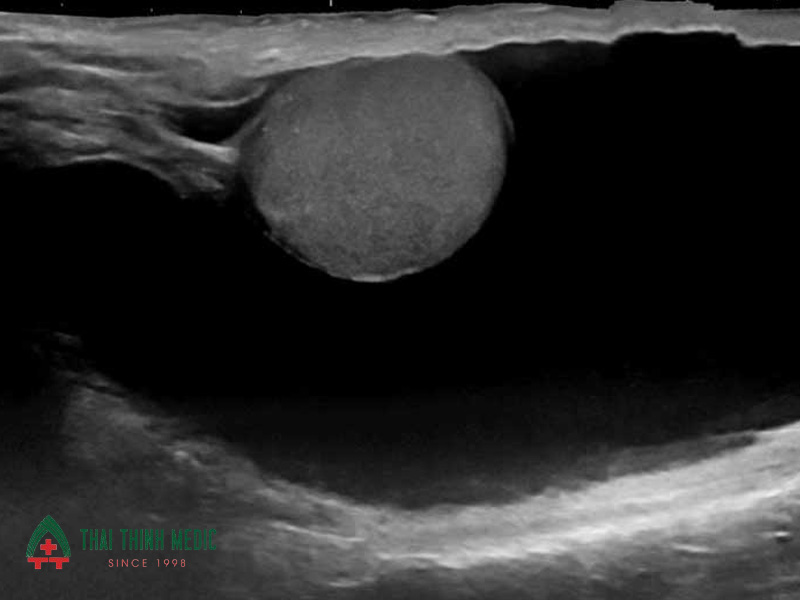

Nang tinh hoàn

Nang tinh hoàn là khối u lành tính chứa dịch hình thành trong hoặc xung quanh tinh hoàn. Phần lớn các trường hợp nang tinh hoàn không gây nguy hiểm, nhưng nếu kích thước lớn có thể gây khó chịu hoặc ảnh hưởng đến sinh hoạt.

Siêu âm tinh hoàn giúp xác định chính xác vị trí và kích thước của nang, đồng thời phân biệt với các khối u khác. Nhờ đó, bác sĩ có thể đánh giá xem nang có cần theo dõi hay can thiệp điều trị hay không.

Nang mào tinh hoàn